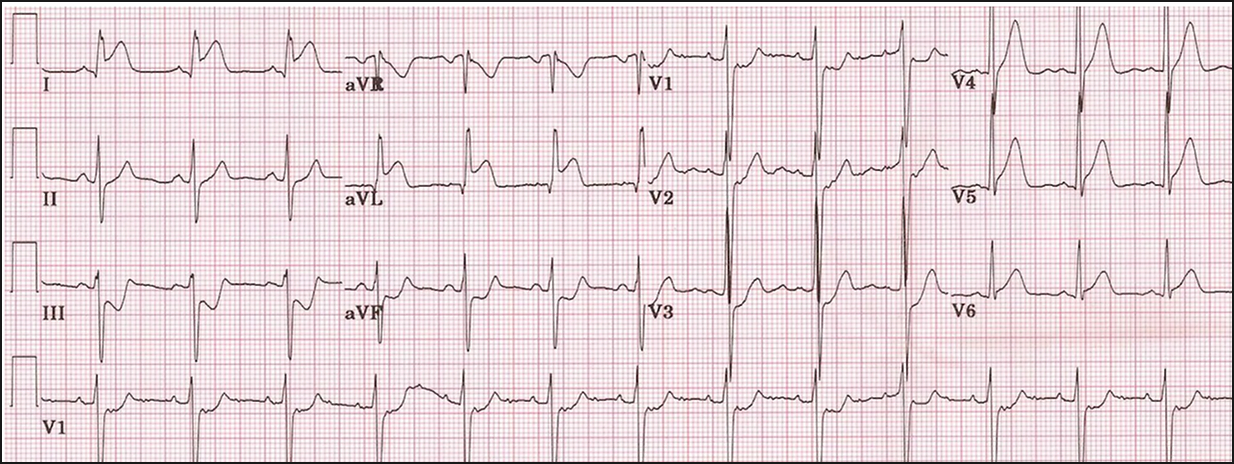

Septal MI:

ST elevation in leads V1 and 2 suggesting a septal MI.

However there is also ST elevation in V3-6 and so other areas of the heart are involved as well

Inferior MI:

This can result from blockage of the right coronary artery. Less commonly it is due to blockage of the left circumflex artery.Because the SAN and AV nodes are supplied by the RCA heart blocks are more common in inferior MIs

There is ST elevation in the inferior leads (II, III, aVF) and there is reciprocal ST depression in lead I and aVL

NSTEMI and Ischaemia:

This is an ECG of an NSTEMI or unstable angina. In lots of the leads ST segment depression can be seen which suggests ischaemia.

This can progress to a STEMI where ST elevation can be seen as well as other features like T-wave inversion